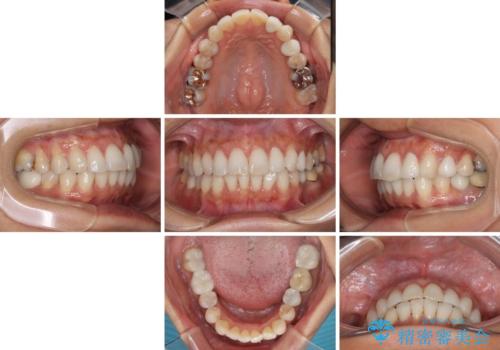

むし歯と前歯のデコボコを治したい インビザラインを使用した総合歯科治療

- 目立つ銀歯やむし歯、前歯のデコボコを気にして来院された患者様です。

デコボコはある程度改善できれば良いとのことでしたので、インビザラインの廉価版を用いて矯正治療を行うこととしました。

しっかりと装着時間を守ってくださり、来院のタイミングに合わせてインビザラインの装着期間を調整するなど、協力いただいたおかけで、1年半の期間で全てを終えることができました。